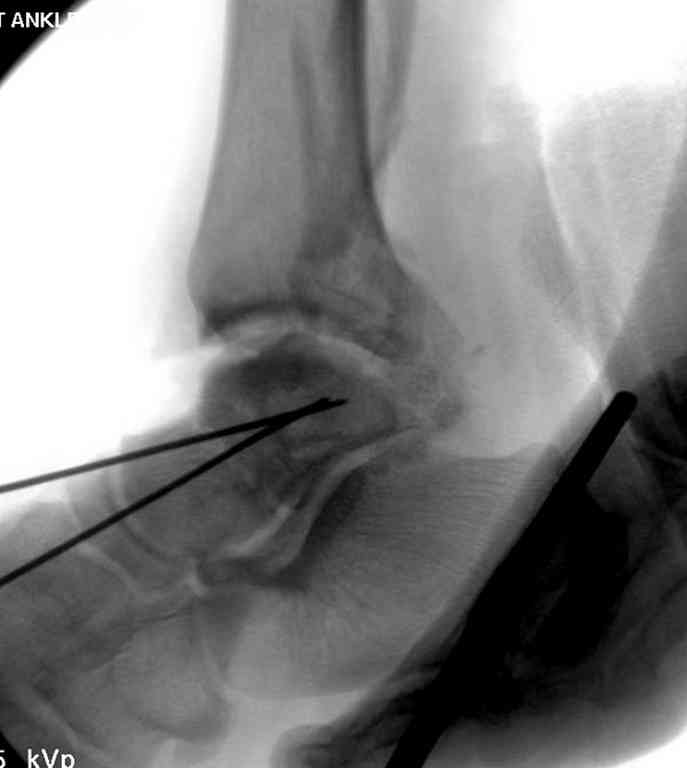

Прооперировали таранную кость, доступ внутренний без пересечения внутренней лодыжки. Хотя покаялись, что не пошли на остеотомию лодыжки внутренней. Винт

провели через небольшой передний доступ.

Джолдас, какими доступами вы пользовались? Какой срок иммобилизации по вашему мнению необходим в моем представленном случае?

При лечении переломов шейки таранной кости очень важно увидеть вторую проекцию шейки, только боковой проекции недостаточно.

В приложении укладка Канале.